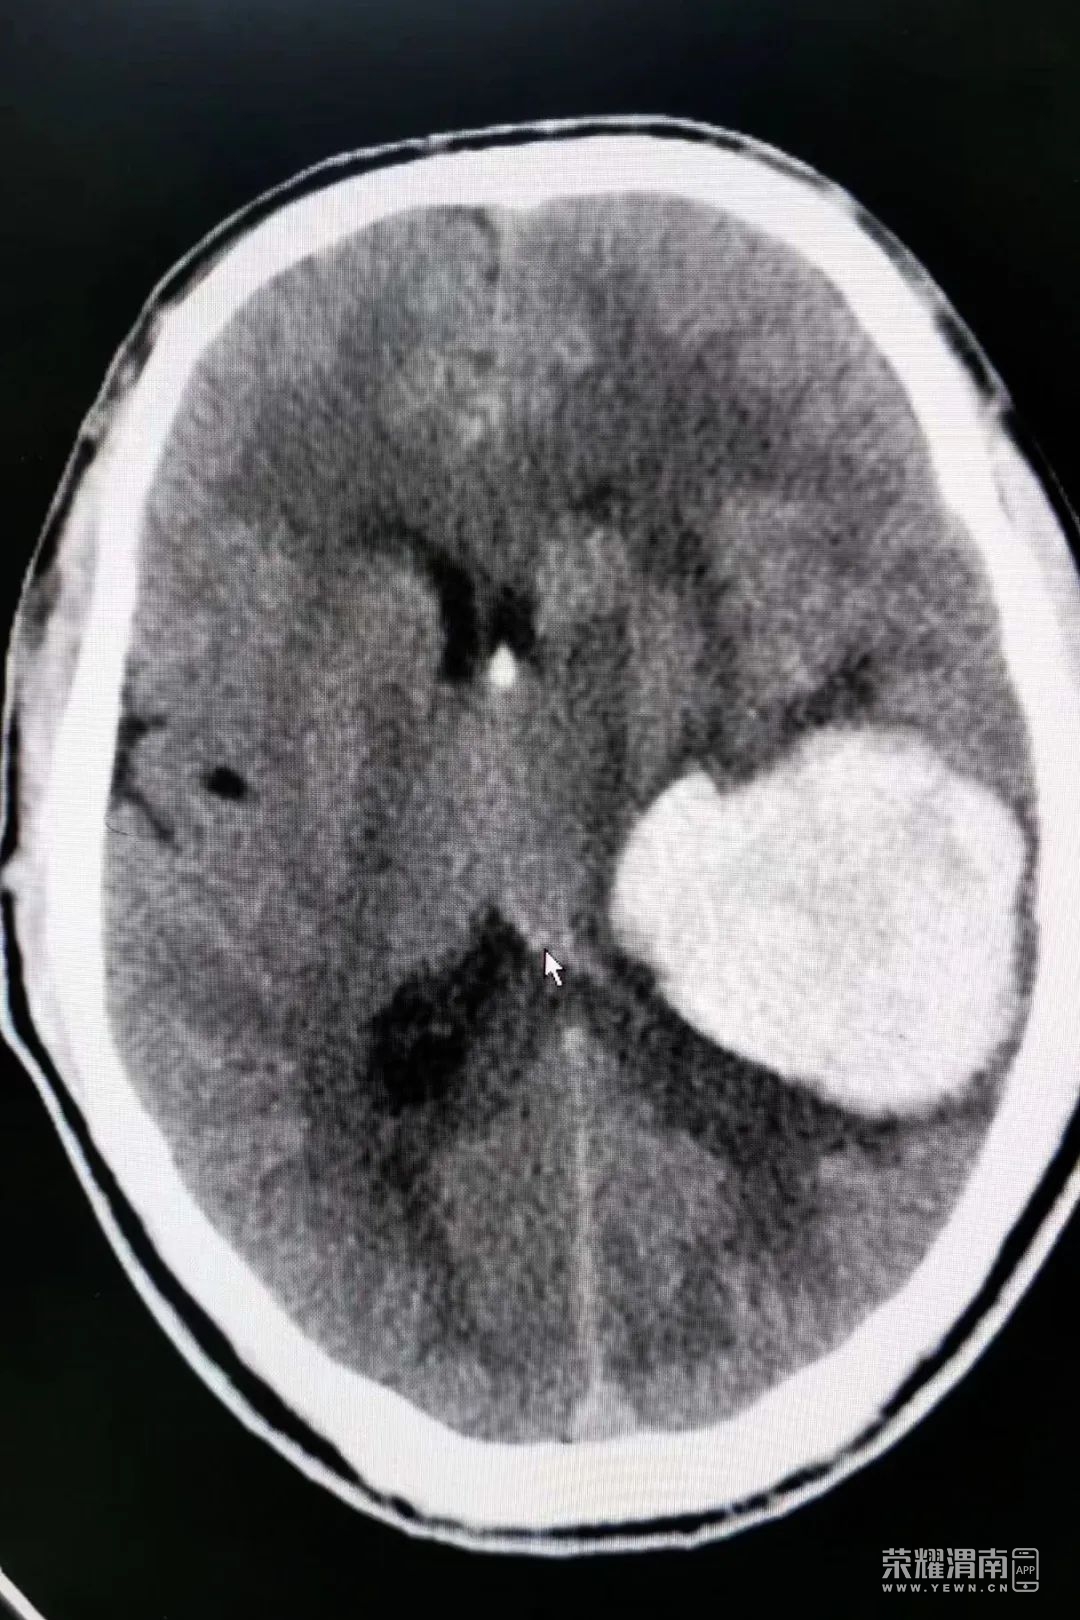

10:30患者入室,查阅病历:患者68岁,晨起跑步时无明显诱因突感恶心,呕吐,呕吐物为黄色胃内容物约100毫升

即出现言语不清,意识丧失,无胸闷气短,无腹胀腹痛。头颅CT显示:右侧基底节区脑出血(约50毫升)诊断为脑出血,患者两侧瞳孔已出现不等大,昏迷状态。情况十分危急。